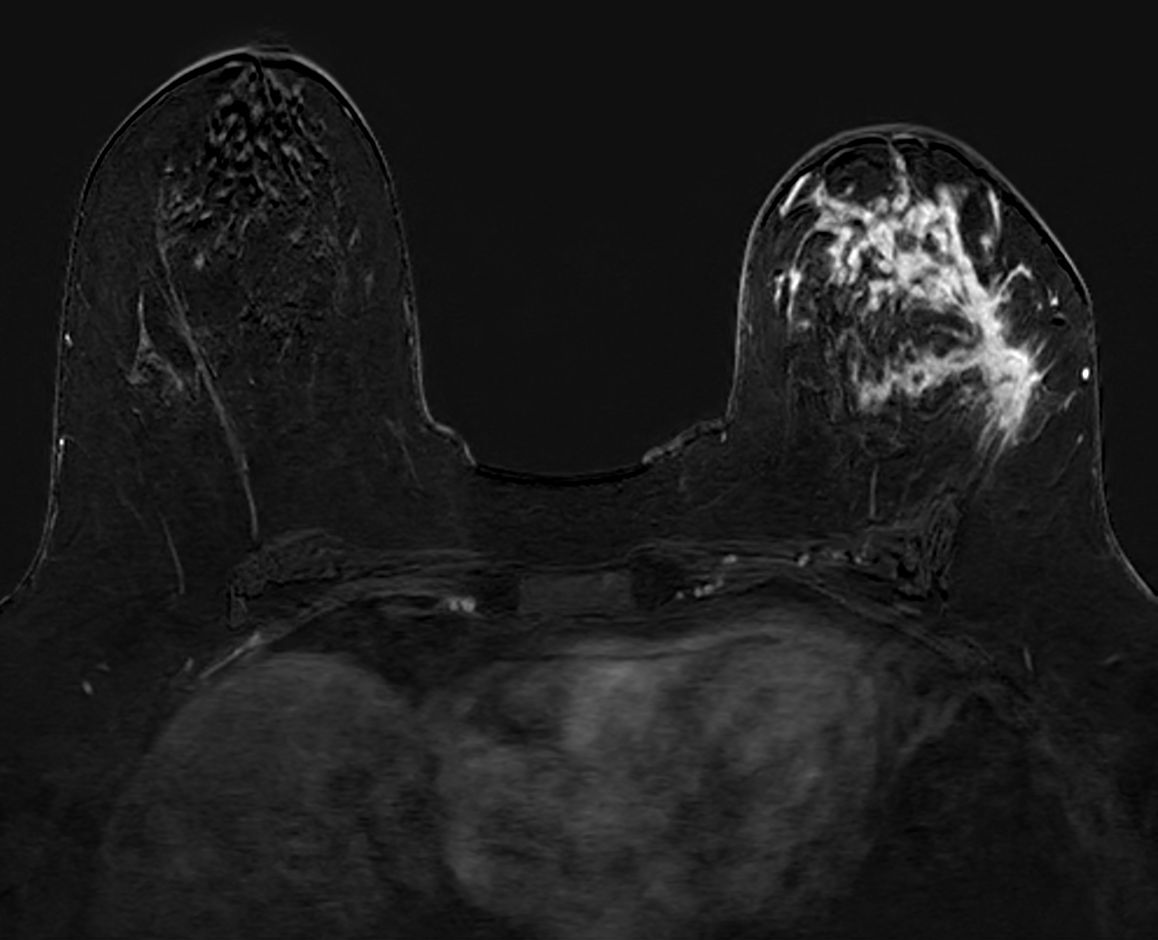

Axial dynamic T1w FFE

Axial dynamic T1w FFE (subtraction)